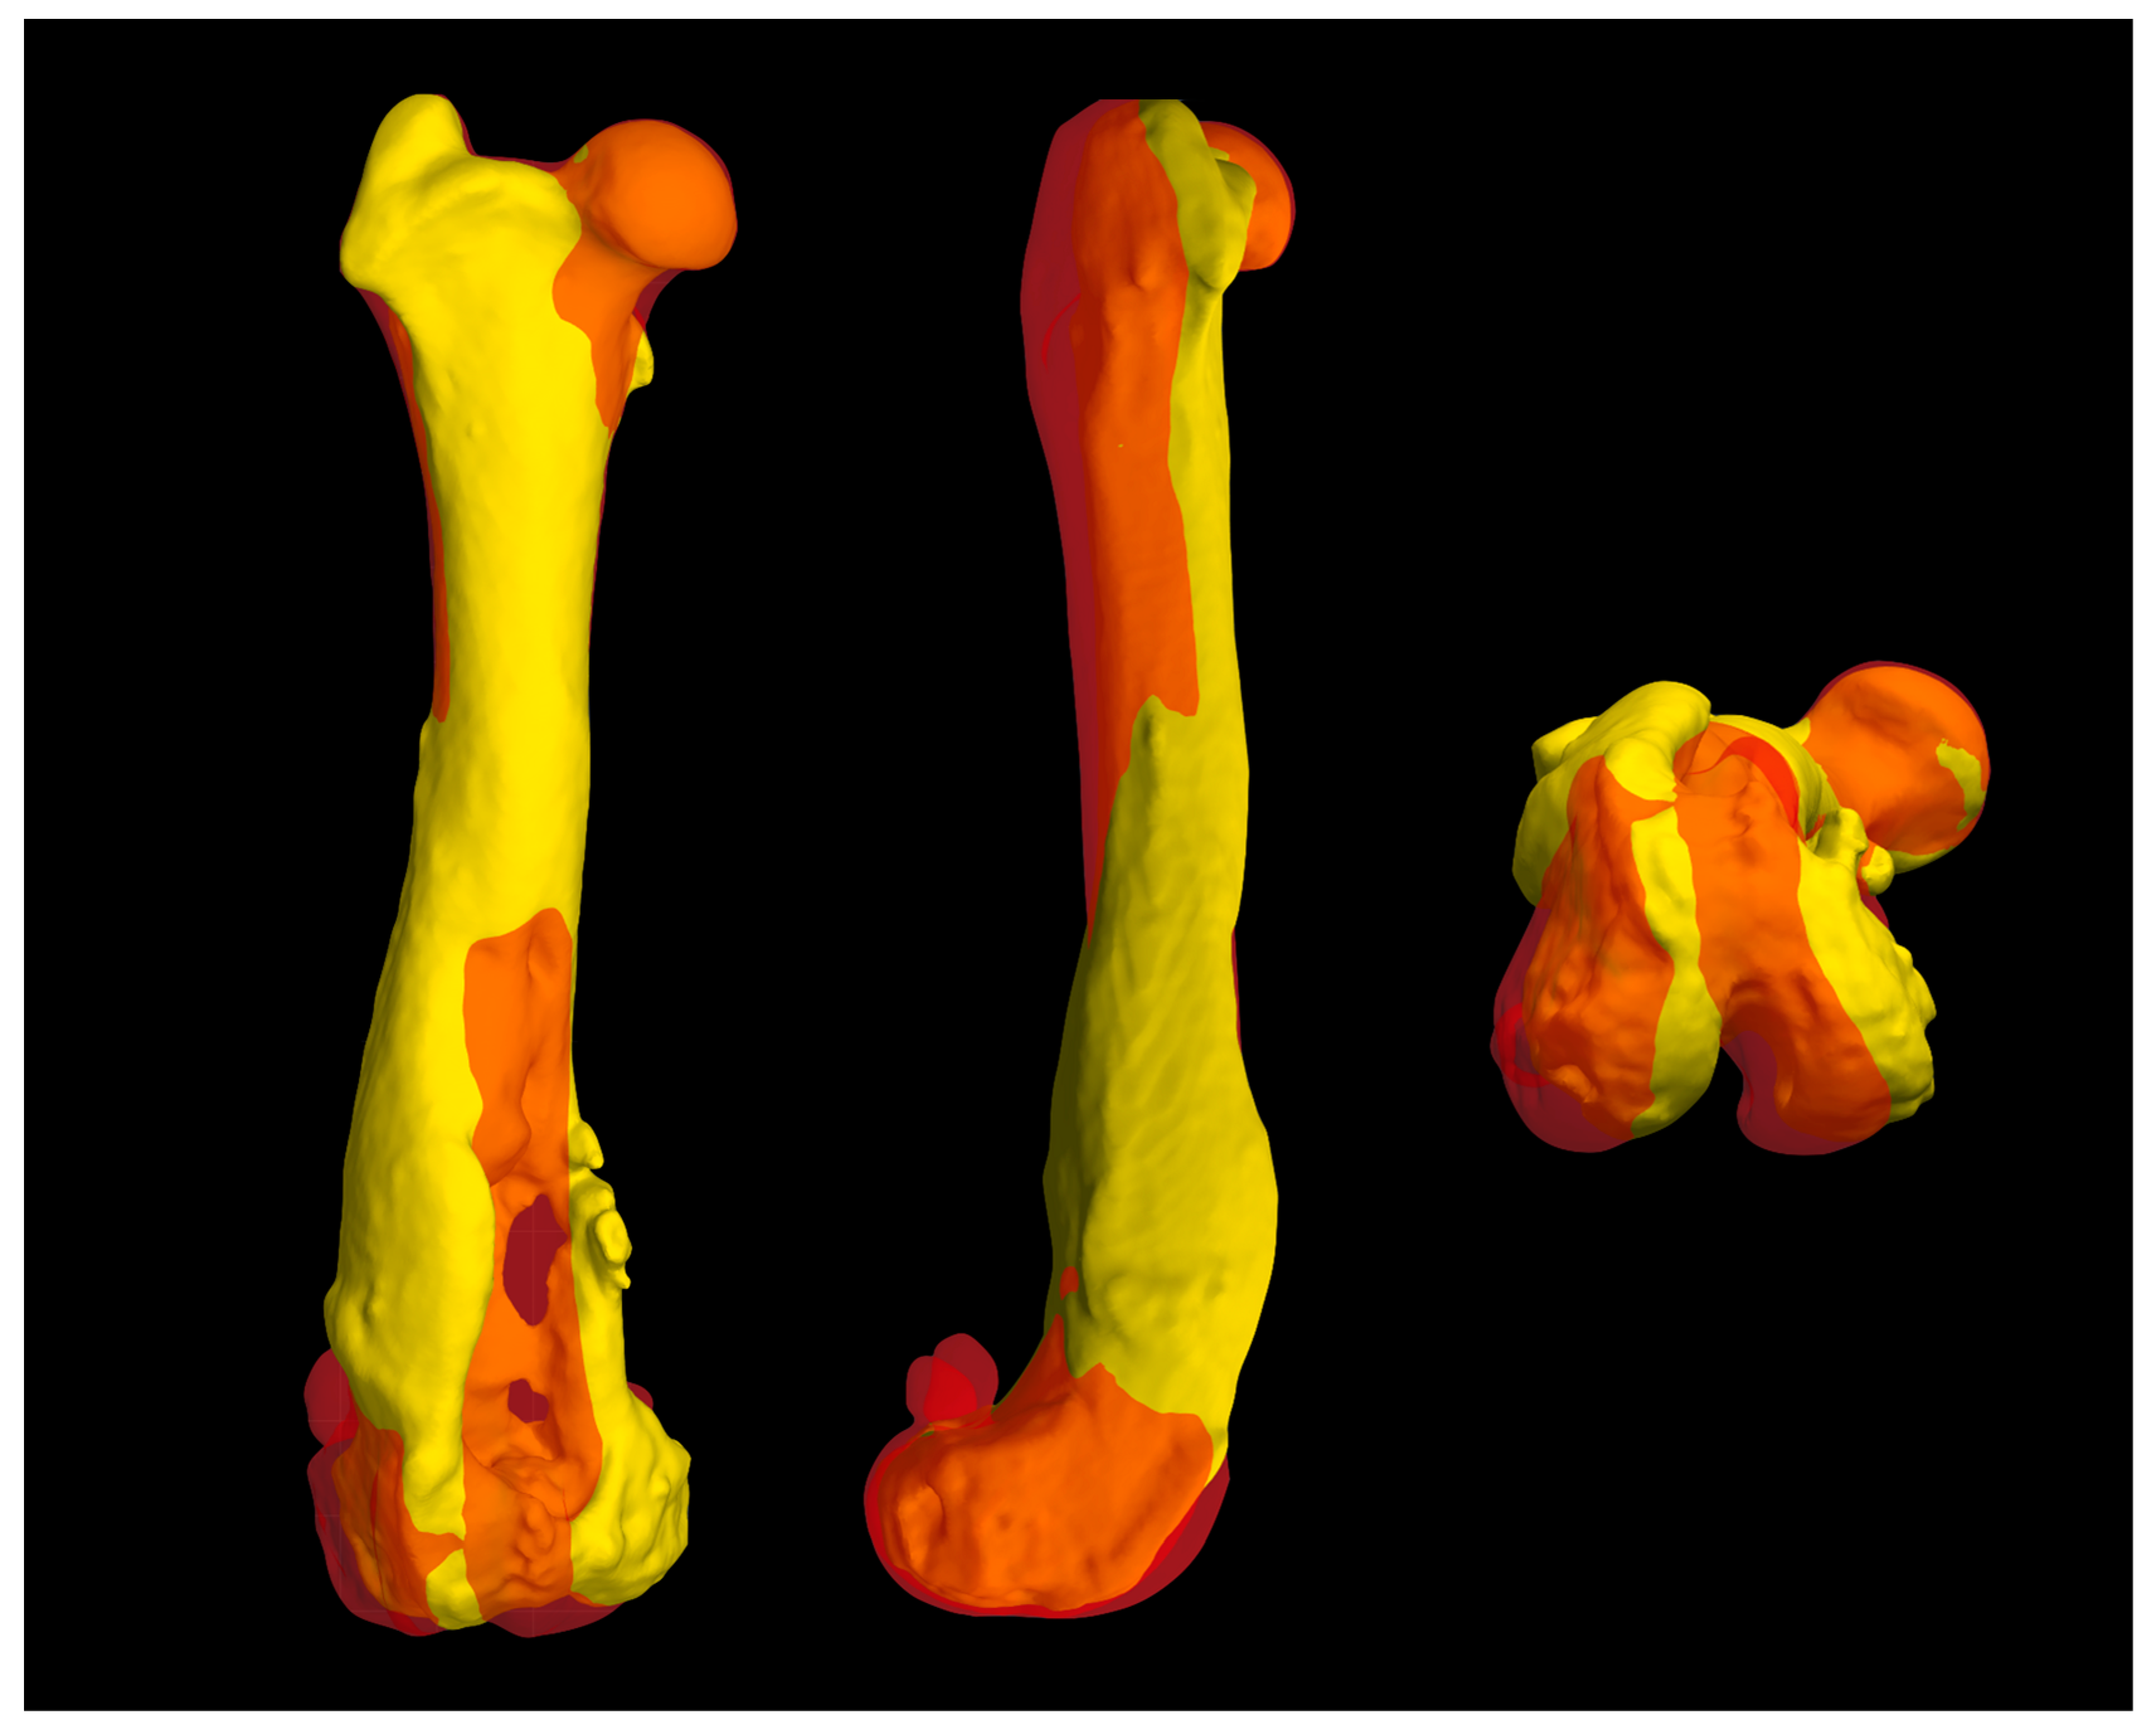

A 3D reconstruction of the hind limbs was performed in order to evaluate their alignment and to design a custom-made PGR: a custom-made implant that fills the bone gap and allows the restoration of the articular surface of the missing femoral trochlea. BonaPlanner computer-aided design CAD software (Bonabyte LLC, Moscow) was used to perform the 3D reconstruction of the hind limbs and the design and manufacture of the cutting guide and custom-made PGR. After uploading the DICOM files of the CT images onto BonaPlanner software, the DICOM files was segmented to STL files to obtain 3D models and allow the imaging processing.

The 3D models of normal and pathological femurs were made using the same software and their superimposition allowed us to observe the presence of a slight distal femur varus of the right hindlimb, so slight as to not require surgical correction. No other differences were detected in the frontal, sagittal and axial planes (Figure 5). Subsequently, the custom-made PGR and the osteotomy guide were designed in order to perform a prosthetic surgery to restore the articular surface of the femoral trochlea and resolve the bone defect.

Figure 5. The superimposition of normal and pathological femur measurements obtained using BonaPlanner computer-aided design CAD software (Bonabyte LLC, Moscow, Russia) allowed to assess the presence of deformities in the frontal, sagittal and axial planes, comparing the pathological right hindlimb and the contralateral hindlimb. The superimposition of the 3D reconstructions showed the presence of a slight distal femur varus of the right hindlimb, which did not require surgical correction.